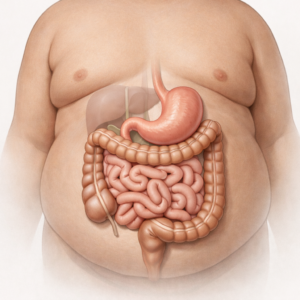

Understanding Abdominal Pain: What Is the Cause?

Abdominal pain is something that almost everyone experiences at some point in…